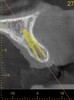

For dental implant-based treatment, the planning phase begins with collection of basic data sets; this is digital touchpoint 1. It includes: (1) a cone-beam CT (CBCT) to view edentulous areas or failing tooth structure, bone, and anatomic landmarks under the soft tissue (Figure 2 through Figure 4); and (2) an intraoral optical scan (IOS) or a scanned model or impression to record the soft tissue and tooth anatomy (Figure 5). The superimposition of the digital imaging and communications in medicine (DICOM) files from the CBCT and the standard tessellation language (STL) files from the IOS allows visualization of how bone, dental structures, and soft tissues relate. Both digital data points are key to implant selection and determining the surrounding bone-grafting needs. An initial treatment plan includes determining the desired implant manufacturer/implant design, size, and positions; these decisions remain the responsibility of the clinician (restoring and surgical team members) and not the technician or planning team.